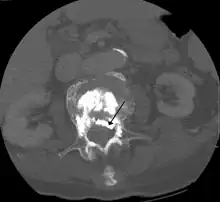

Some of the associated risks are from the leak of acrylic cement to outside of the vertebral body. Although severe complications are extremely rare, infection, bleeding, numbness, tingling, headache, and paralysis may ensue because of misplacement of the needle or cement. This particular risk is decreased by the use of X-ray or other radiological imaging to ensure proper placement of the cement.[2] In those who have fractures due to cancer, the risk of serious adverse events appears to be greater at 2%.[23]

During the procedure, bone cement is injected with a biopsy needle into the collapsed or fractured vertebra. The needle is placed with fluoroscopic x-ray guidance. The cement (most commonly poly methyl methacrylate (PMMA), although more modern cements are used as well) quickly hardens and forms a support structure within the vertebra that provide stabilization and strength. The needle makes a small puncture in the patient's skin that is easily covered with a small bandage after the procedure.[2]